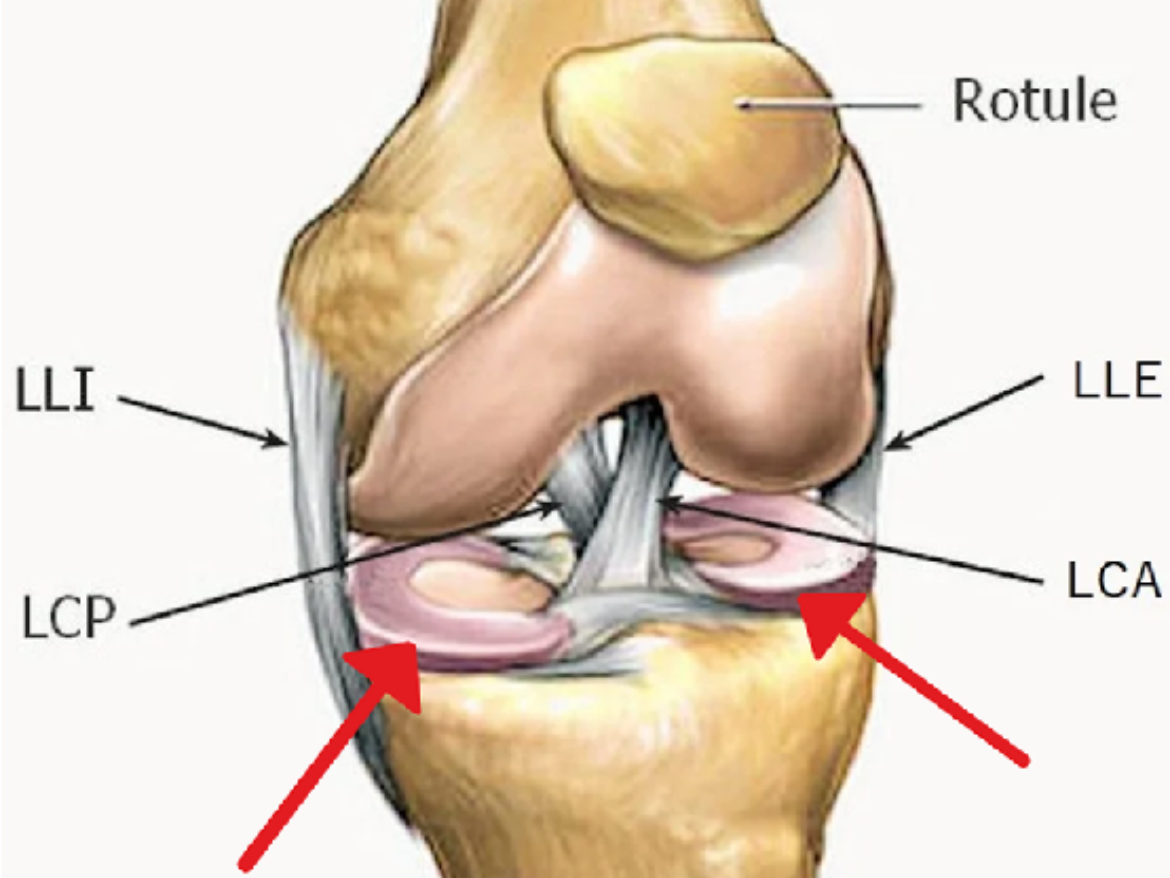

La surface de contact entre les condyles fémoraux et le plateau tibial est augmentée par deux structures circonférentielles en forme de croissant fixées sur le plateau tibial, de consistance élastique assez rigide et de section triangulaire, appelées ménisques. Il s’agit du ménisque médial et latéral, qui amortissent l’appui du fémur sur le tibia, mais participent également à la stabilité du genou.

L’articulation est enveloppée d’une membrane malléable mais résistante à la déchirure, appelée capsule articulaire. Celle-ci assure l’étanchéité de l’articulation, empêchant la fuite du liquide synovial. Une deuxième enveloppe circonférentielle formée de ligaments, dont surtout les ligaments collatéral interne et collatéral externe, maintient le genou et l’empêche de se désaxer en varus (genoux en O) ou en valgus (genoux en X).

Au centre de l’articulation, deux ligaments puissants stabilisent le genou dans les mouvements de rotation et de translation en avant ou en arrière. Il s’agit des ligaments croisés (antérieur et postérieur), qui constituent ce qu’on appelle le pivot central du genou. Deux groupes musculaires principaux font bouger le genou: Les ischiojambiers en arrière pour la flexion, et le gros muscle quadriceps en avant pour l’extension. Ce dernier est primordial pour la station debout et la marche. Il est en continuité avec la rotule, puis se prolonge par le tendon rotulien qui s’insère sur le tibia proximal: C’est l’appareil extenseur du genou.